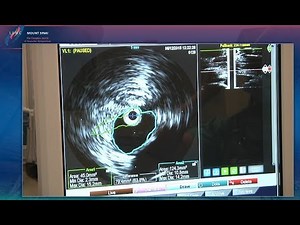

Endoscopic Septoplasty

Basic surgical technique